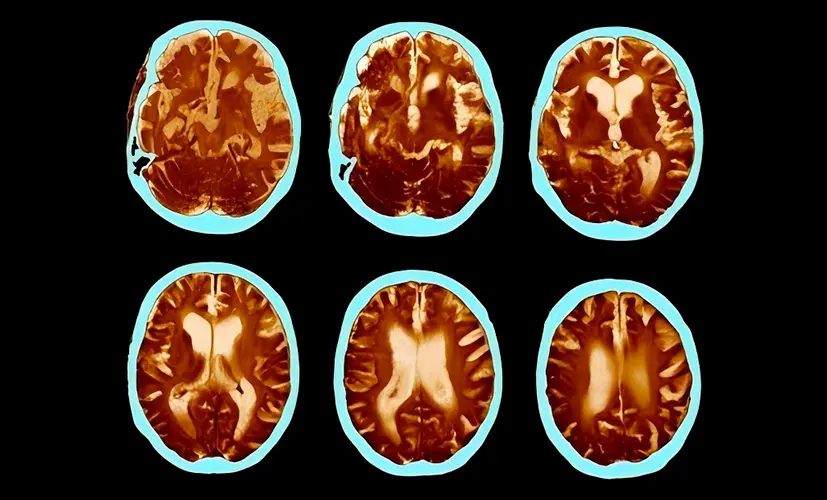

Cognitive decline is a disorder of brain function caused by pathological changes in the body. In this article, you'll learn about the causes, mechanisms, and warning signs-when it's time to take action. We'll also cover the serious complications of this insidious condition and the modern treatment options available.

– Cognitive decline and brain fog are like ticking time bombs in a person's mind. For years, they may seem like minor annoyances-forgetfulness, some fatigue, more difficulty concentrating. But then, without warning, disaster strikes. As a neurologist, I've witnessed tragedies that changed people's lives-and their families-forever. Let me share five terrifying consequences of ignoring these "silent" conditions. This isn't fiction. This is what I see in my clinic every day.

1.Complete memory loss - a life without clarity

The neural pathways in the brain become so damaged that no supplement can help. The person permanently loses their ability to recall memories. Relationships deteriorate. Confidence shatters. Depression takes hold. I've seen patients who isolated themselves at home, unable to face their loved ones.

2. Dementia - the silent thief

Untreated cognitive decline can evolve into dementia. It may start as occasional forgetfulness, but before you know it, the condition has spread, impairing judgment and daily function. Patients describe the mental haze as a fog they can't escape. Most are diagnosed too late-when little more can be done.

3. Brain fog leading to chronic fatigue

Inflammation spreads from the brain to affect overall neurological health. The result? A mind that slowly shuts down. Mental exhaustion becomes your new norm-struggling to think clearly, day after day, as your body weakens. I've seen individuals beg for relief that never arrives.

4. Stroke caused by impaired blood flow

Cognitive decline is often the first sign of poor vascular health-not just in the brain. If ignored, a clot could strike, causing a stroke. I've seen seemingly healthy 45-year-old individuals on the operating table, fighting for their lives, all because they assumed their "lapses" were just a part of aging.

5. Nerve damage and mental confusion